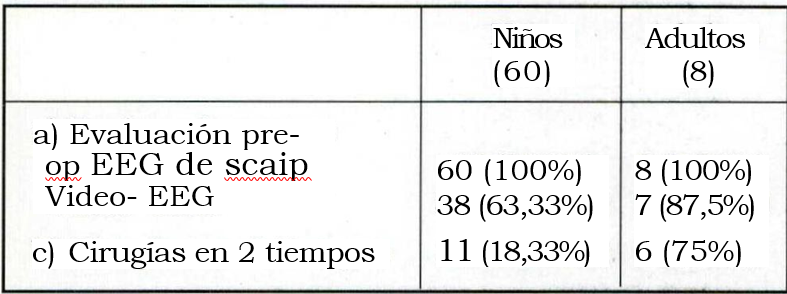

Los exámenes neurológicos realizados se resumen en la tabla 5 y la localización de las lesiones en la tabla 6.

Tabla 5. Exámenes neurofisiológicos

Es importante remarcar el aporte que significó el advenimiento de las nuevas técnicas electroencefalográficas en la selección del candidato a cirugía. Hacia fines de 1995 y comienzo del '96 se inauguraron en el país las primeras unidades de Video-telemetría, lo que mejoró y enriqueció el estudio de los candidatos. Esto permitió llegar a la cirugía con información suficiente para reducir el porcentaje de decisiones intraoperatorias, que dependían de la ECoG, con un potencial margen de error derivado del factor anestésico. La videotelemetría se efectuó en 47/68 (69,1%) de los pacientes. Los 21 pacientes operados sin Video-telemetría prequirúrgica tenían lesiones extensas con buen correlato con la clínica y el EEG prolongado computarizado (Fig. 1).

A 7/8 adultos se les efectuó videotelemetría. El restante había sido operado 5 meses antes de un glioma frontal grado II.

En 11/60 pacientes estudiados con videotelemetría fue necesario recurrir a la utilización de electrodos intracraneanos9. Esto implicó efectuar cirugías en dos tiempos: uno inicial para la colocación de los electrodos y el traslado del paciente a la unidad de Video-telemetría; luego de captar un número suficiente de crisis, no menos de 3 a 5, se realizó segundo tiempo quirúrgico acorde a la estrategia definida previamente. (Figs. 3 y 4).